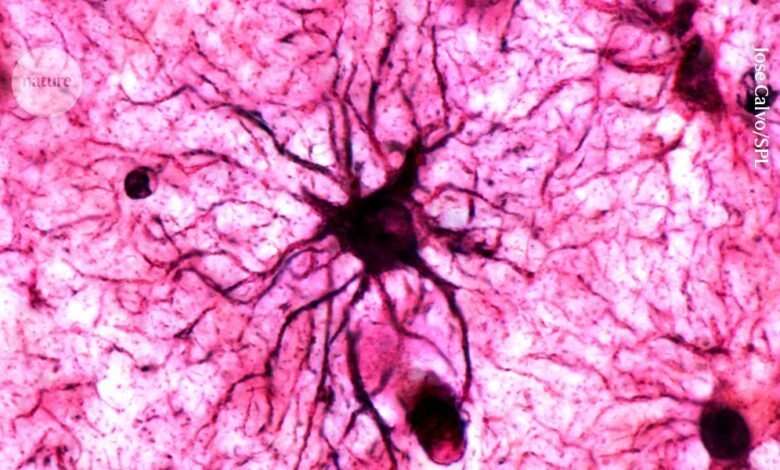

A type of brain cell called astrocytes play a crucial role in stabilizing memories in the brain.Credit: Jose Calvo/SPL

يلعب نوع من خلايا الدماغ يسمى الخلايا النجمية دورًا حاسمًا في تثبيت الذكريات في الدماغ.الائتمان: خوسيه كالفو / SPL